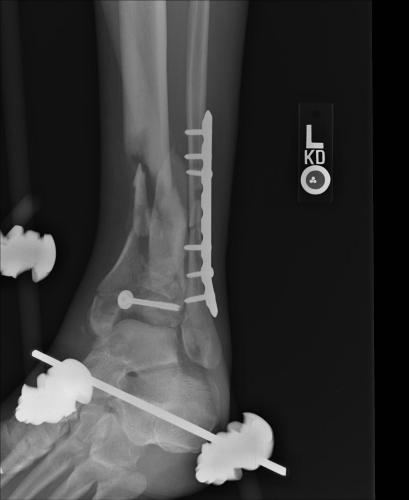

Pre-corrective surgery X-Rays of the damaged right & left legs / ankles

These x-rays were taken at Dr Armendariz’s office, just prior to performing any corrective surgery. As can be seen in these images,

there was no tibia bracing provided by Dr. Keller. Liam was released from Dr Keller’s care with instructions that full weight bearing could

be accomplished within 2 months of Keller’s last surgical procedure. The best example to examine is the second image (from the left) of the

top how. Notice how the bones that should be aligned with the tibia are in fact on the other side of the leg. The third image shows how badly

Liam’s left foot was twisted as a result of the pool placement of the external fixation. What is not obvious is that the screw at the bottom

of the plate on the right fibula missed being screwed into the plate.